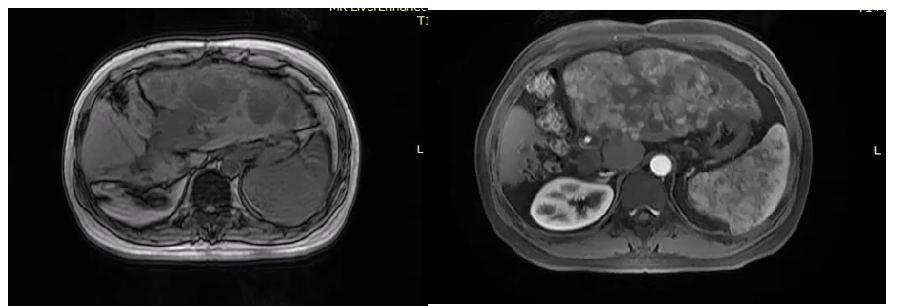

2021年7月27日MR提示,肝癌综合治疗后,病灶活动,大小约18.2cm×8.9cm,门静脉左支癌栓;肝门区淋巴结显示;肝硬化,腹水(图1)。

图1. 2021年7月27日MR